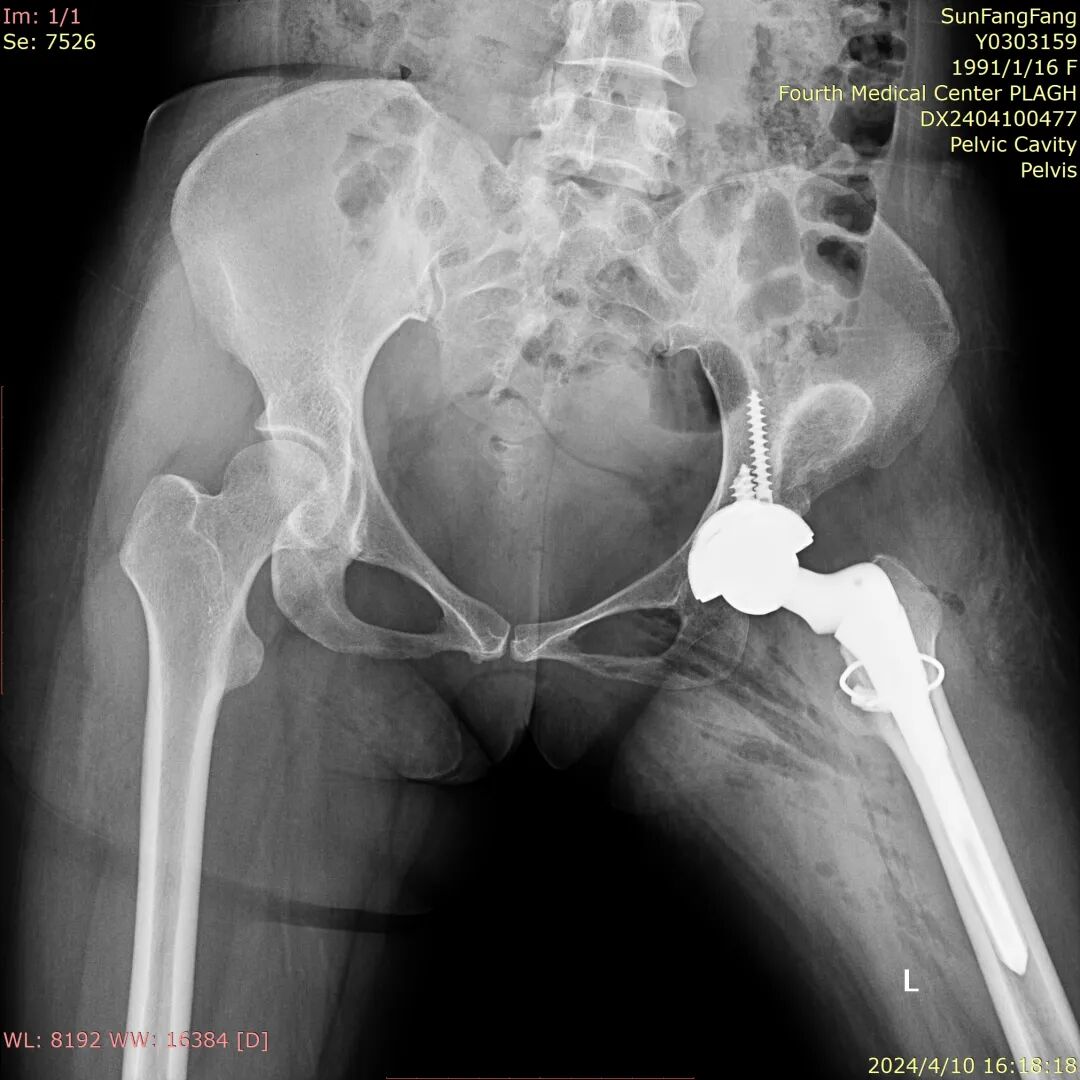

术后结果